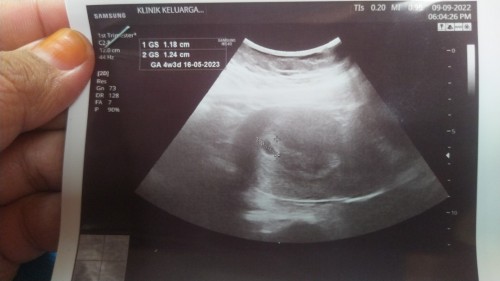

Normal ke klau scan 6 minggu 6 hari x nmpak janin lg?

saya pn bru scan 6 minggu x nampak lgi

boleh jd normal. repeat shj slp 2mgg

saya 4minggu 3hari dh nampak kantung

saya scan 4w 3d nampak kantung shj

Normal.. Sy 8 minggu baru nampak..